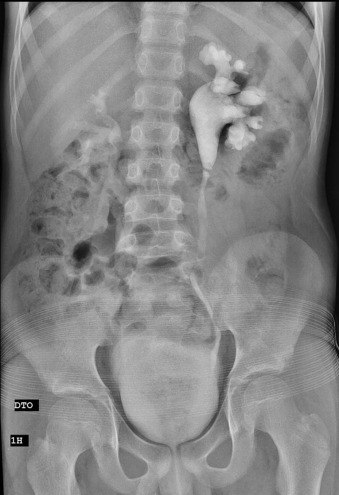

A urografia endovenosa mostrou uma imagem de subtração transversal ao nível da JPU (fig. 1 ), confirmada por tomografia axial computorizada (TC), com fase excretora, revelou vasos polares inferiores e obstrução ao nível da JPU esquerda sem défice funcional significativo, uma vez que a excreção ocorreu num tempo precoce.

Urografia endovenosa mostra uma imagem de subtração transversal ao nível da JPU.

Ambos os exames de imagem pareciam apontar para uma obstrução da JPU por um vaso anómalo polar inferior, carecendo de confirmação por angio‐TC.